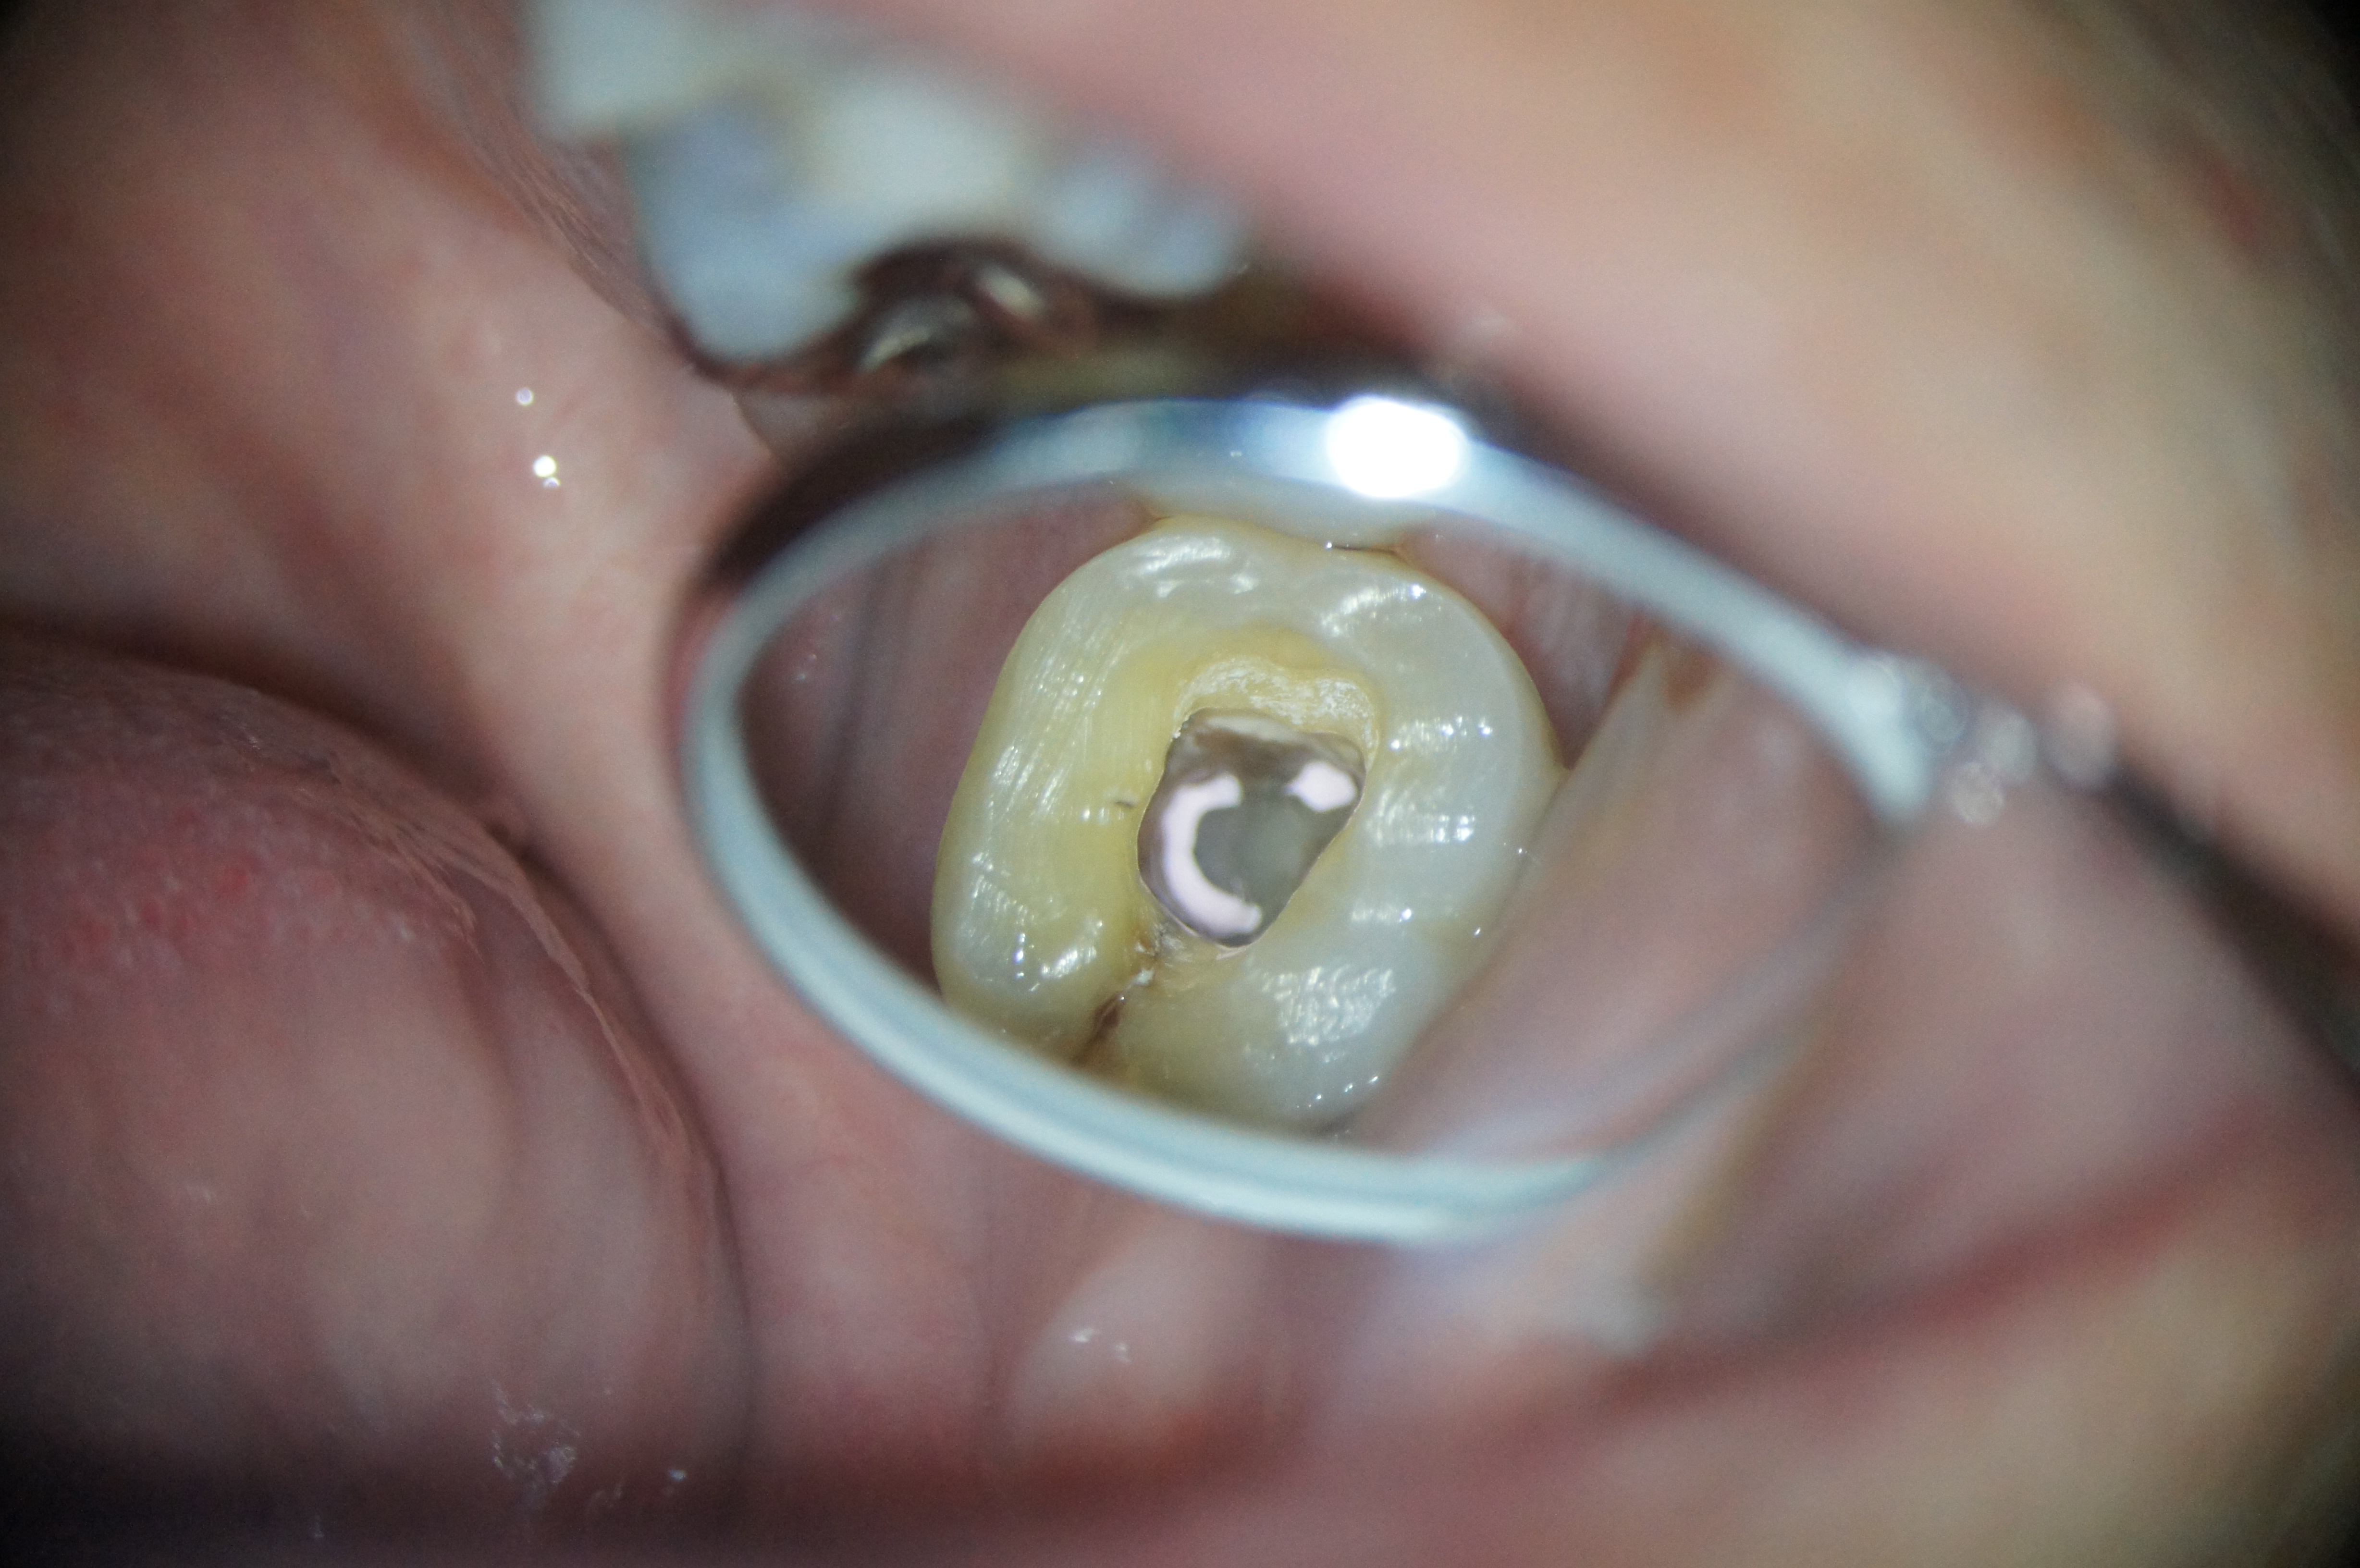

中心結節

歯の中心になにか見えますね?

これは中心結節といわれるもので、歯の形態異常のひとつとされ、初発部位は下顎第二小臼歯です。1~4%程度の頻度で現れるらしいです。

この結節自体は特に悪いものではなく、問題ないのですが、形態的に折れやすいことが問題です。

さて、中心結節がある場合は、そのツノの中心に神経が存在することがあります。

もし、中心結節が折れてしまった場合、その中には神経が走行していますのでそこから容易に感染します。

感染した後は、痛みがでるかもしれませんし、出なくても早々に神経は壊死してしまうので、歯の神経をとる処置が必ず必要になります。

また、もし、中心結節の存在を本人、周りの人が知らなかった場合を想像してみてください。歯は痛いんだけど外からは、結節が折れることにより、普通の外観の歯が、言い換えるなら一見して健康に見える歯があることになります。何で痛いのかなぜ処置が必要なのか理解不能な状態に陥ると思います。